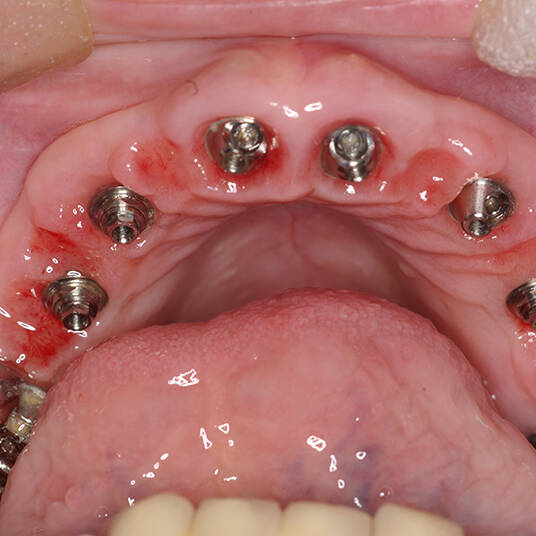

Na Clínica Pontes Odontologia, somos referência em implantes dentários em Fortaleza, oferecendo tratamentos de alta qualidade e tecnologia de ponta. Os implantes dentários são estruturas de titânio posicionadas cirurgicamente no osso maxilar ou mandibular para substituir as raízes dos dentes ausentes. Essa técnica permite a fixação de próteses personalizadas, restaurando a função mastigatória, a estética e a autoestima dos nossos pacientes.

Utilizamos a tecnologia CAD CAM, um sistema avançado que possibilita a confecção precisa das próteses dentárias diretamente sobre os implantes. Esse método inovador garante um ajuste perfeito, um resultado estético superior e proporciona muito mais conforto e durabilidade. Com o CAD CAM, nossos pacientes contam com um processo mais rápido e previsível para alcançar o sorriso desejado.